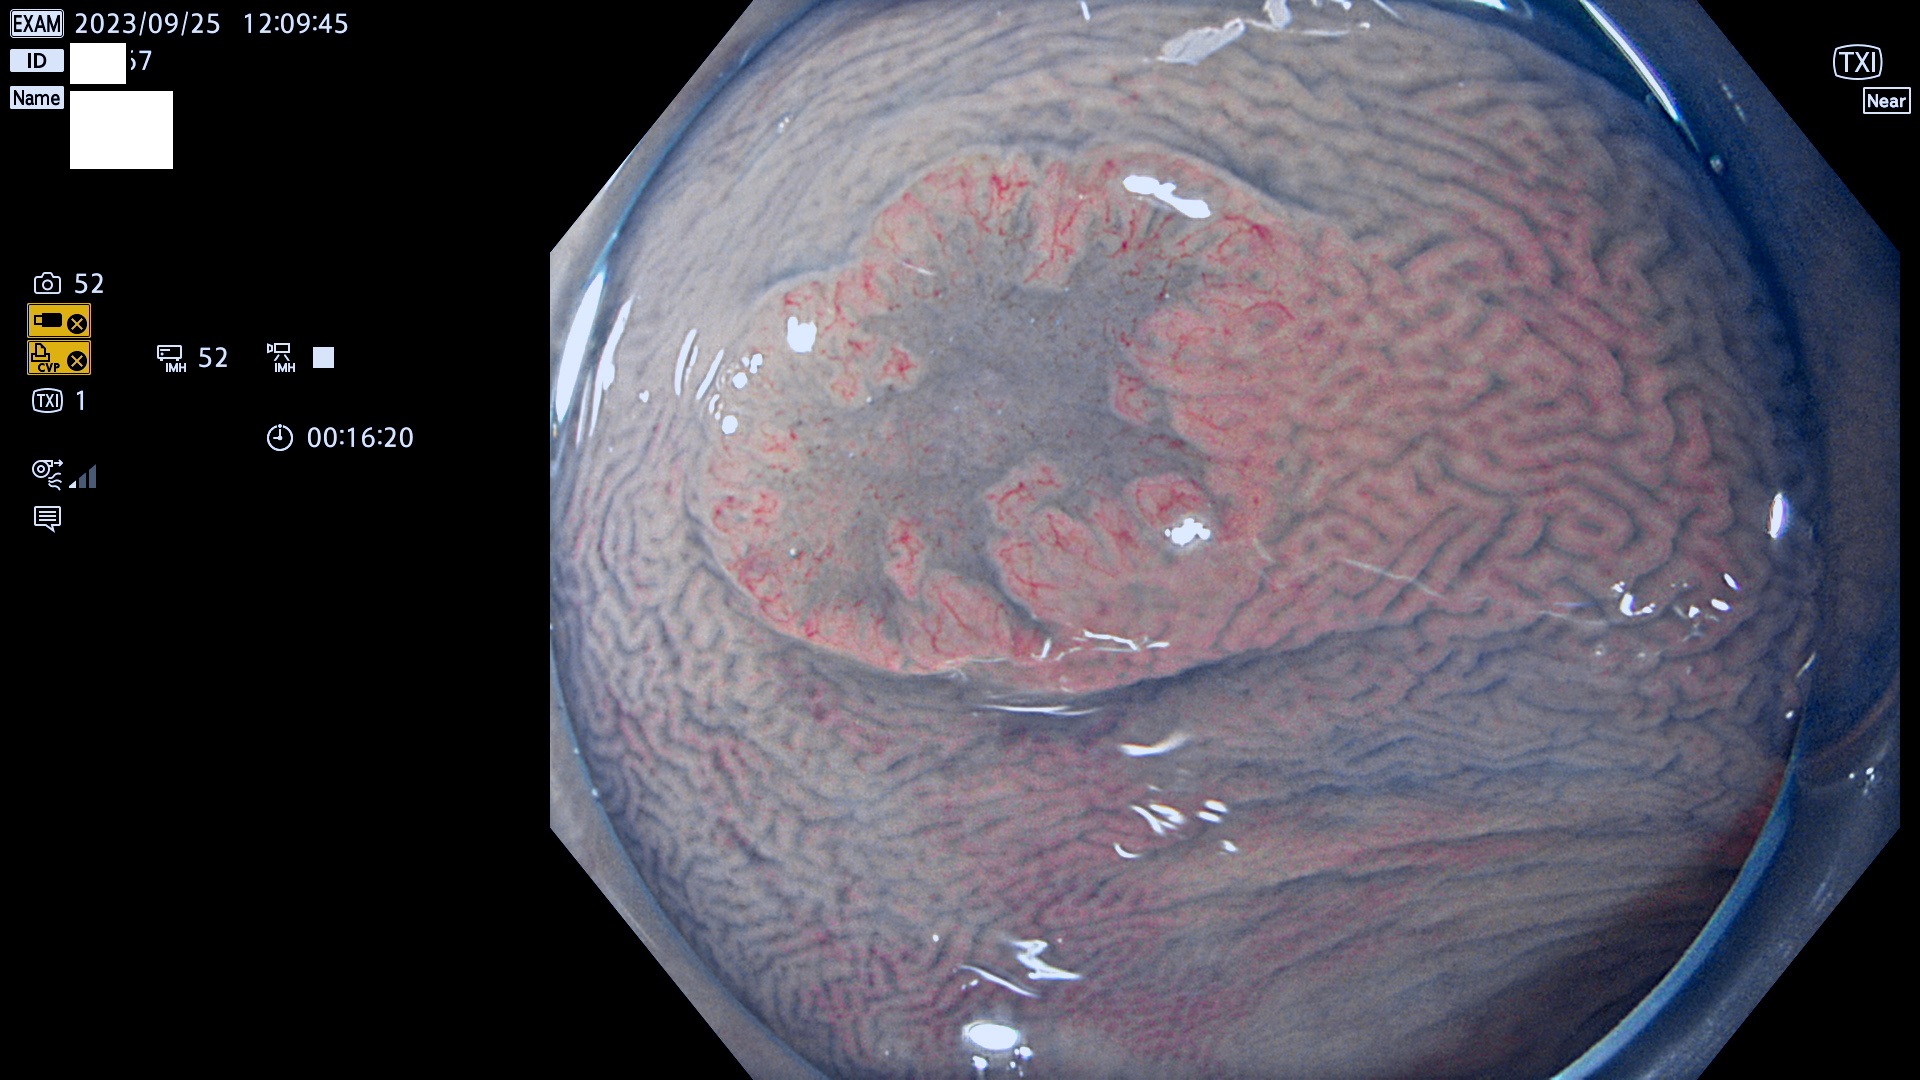

表面型腺腫(Flat Adenoma)の中で、完全に平坦な物をUb、陥凹している物をUcと呼びます。平坦隆起型(Ua)よりも、発見が難しく危険な病変です。このタイプは「内視鏡後・大腸癌の重要犯人」であり、この発見率は「腺腫発見率」よりも、重要な意味があります。

専門的)何故、陥凹していると危険? 癌遺伝子の変異が蓄積すると細胞分裂が盛んになり隆起するのでは?と通常は思われるでしょう。しかし実際は逆です。これは2022年の記事にある「細胞はストレスに直面したら細胞分裂を止める(細胞老化に入り休眠する)という生命の基本的現象」によるものです(Oncogene Stress)。細胞老化を起こすのが癌抑制遺伝子で、この安全装置(ブレーキ)が壊れると癌になります(休眠からの覚醒)。ですから陥凹は「まだ癌では無いが癌化の直前」を意味します。特に「小サイズなのに陥凹している」病変は短期間に腫瘍進化(⇒2021年記事)が起きたことを意味します(=ゲノム不安定性

専門的)Uc=De Novo癌? 内視鏡の解像度が低かった時代、このような説もありました。しかし今日の高精度内視鏡では良性の微小なUc型腺腫が日常的に見つかります。私見ですが「Ucこそが多段階発癌(Adenoma-Carcinoma Sequence)のMain Route」と考えます。

毎週の検査(木・金・土・日)に発見されたUb、Uc型・腺腫を、その週の日曜の夜にUPし1週間、提示します。

抽出の対象期間 2023年9月21日(木)〜9月25(月)の5日間(60件の検査)8件